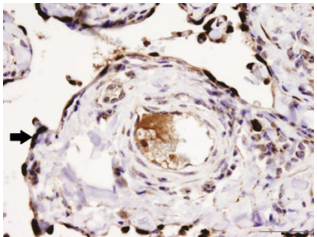

Histologic section from a submandibular fluid-filled mass in a horse. Dx? What are the cells + for? Describe.

Dx: Reactive lymphoid cell population, consistent with lymph fluid from an obstructed duct.

PROX-1 staining of the nuclei of lymphatic endothelium lining the channels of the mass (arrow), while normal vascular endothelium fails to stain.

What is your diagnosis? Fluid surrounding a submandibular mass from a horse. Vet Clin Pathol 42/4 (2013) 531–532.